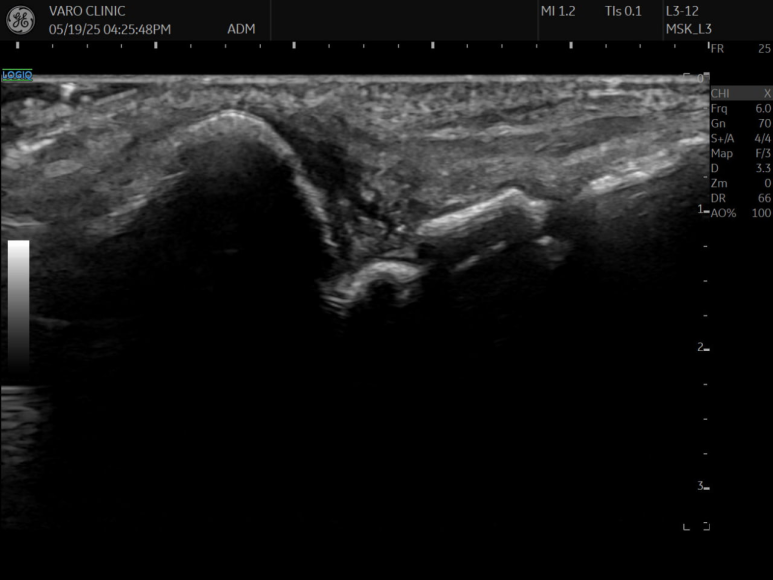

제가 1억이 넘는 GE초음파 최상위 기종

LOGIQ FORTIS를 쓰고 있는데

사람에 따라서

요골 부착부나 척골 부착부쪽은

안 보일 때가 있습니다.

양방 초음파든 한방 초음파든

삼각섬유연골의 전체 범위를 볼 수 없어서

확실하게 진단할 순 없고요.

반드시 MRI를 찍어봐야 합니다.

초음파는 개인 의원급에서

일차적으로 확인하는 목적이 크고요.

MRI 검사를 바탕으로

주사 놓을 때 가이드 목적으로

초음파를 사용하는 겁니다.